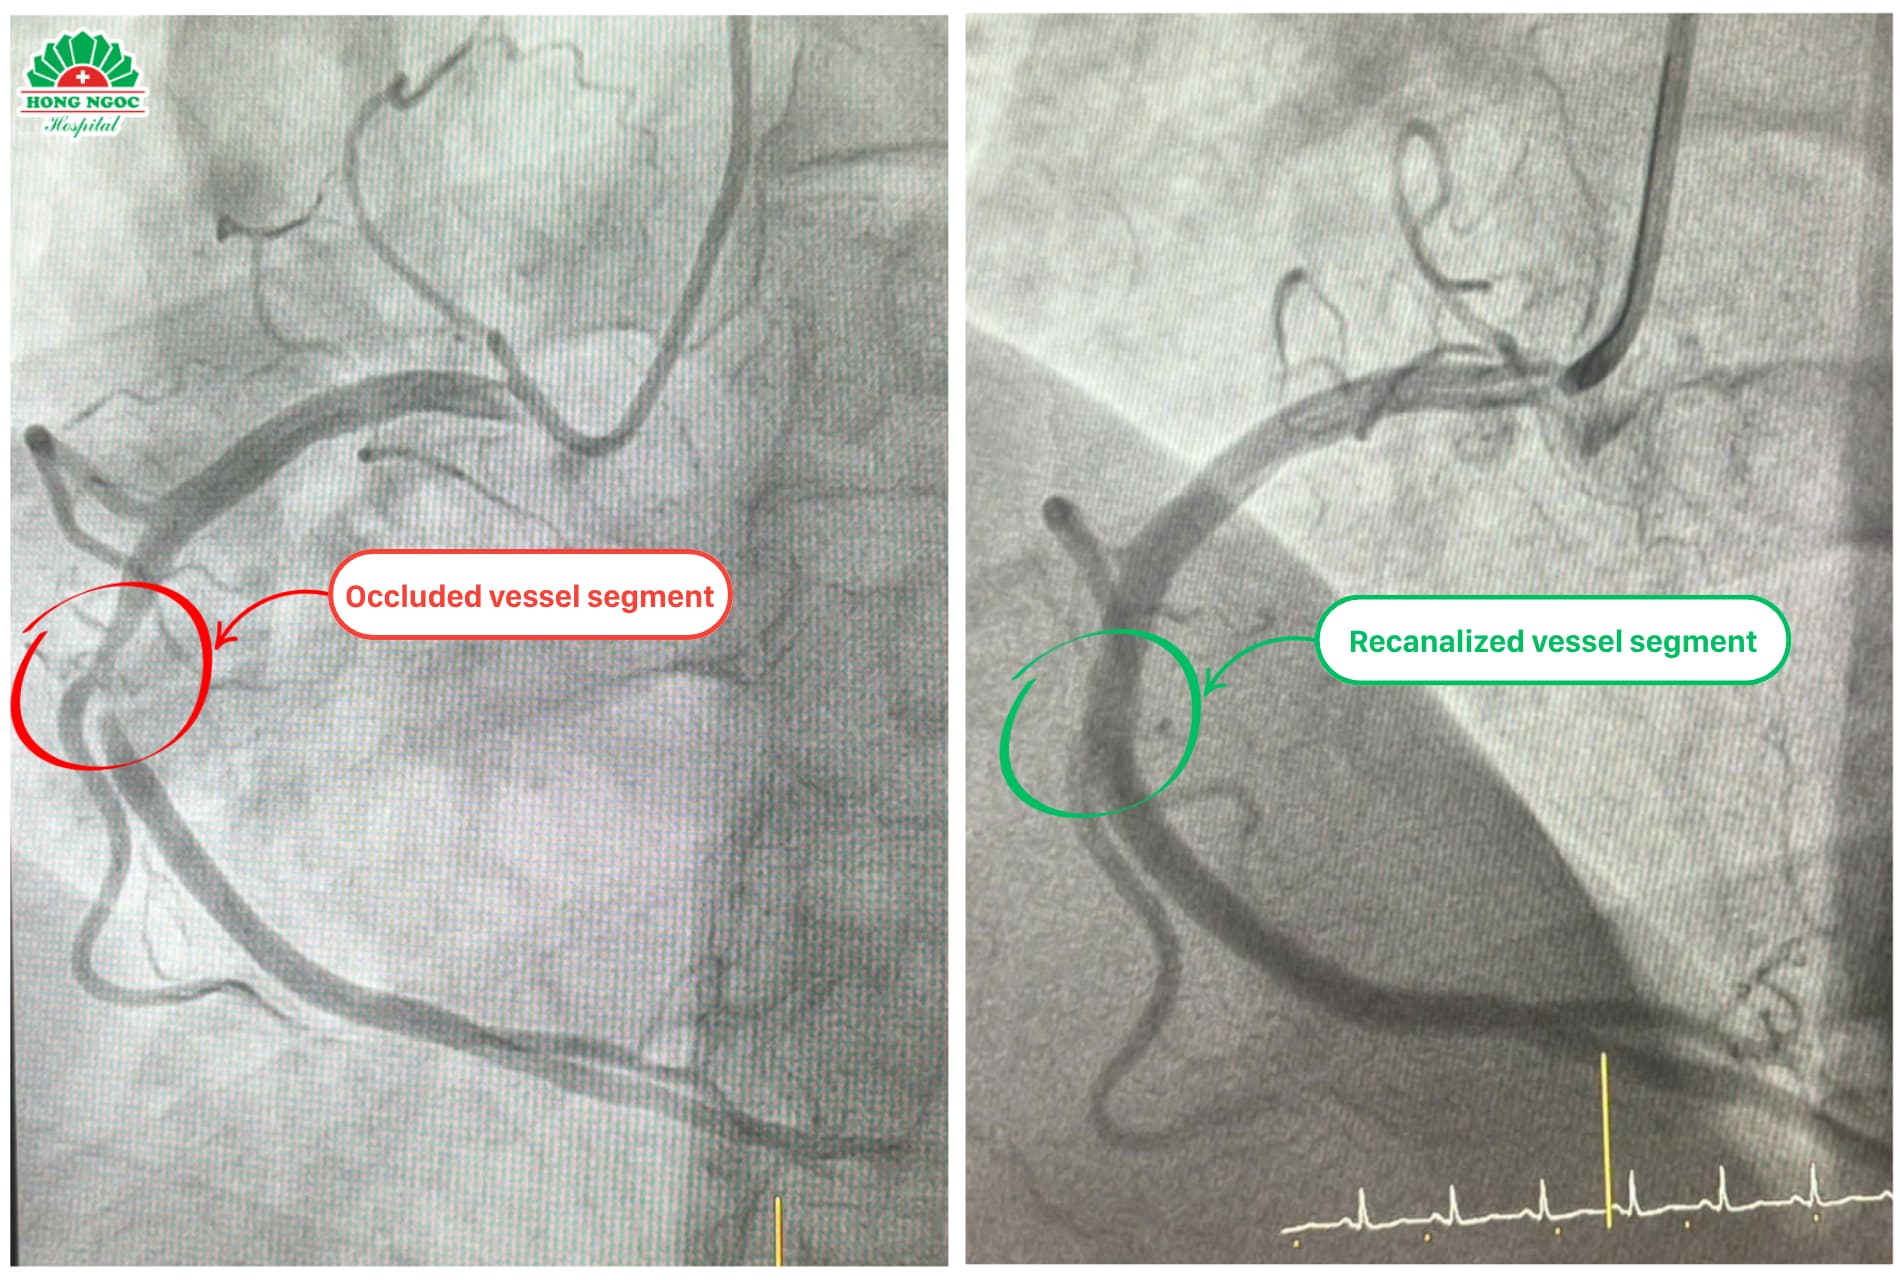

Recognizing the critical condition, the medical team promptly activated the hospital’s acute myocardial infarction emergency protocol. The patient underwent coronary angiography using an advanced Digital Subtraction Angiography (DSA) system, the imaging revealed severe stenosis in segment II of the right coronary artery, one of the heart’s main blood vessels. To restore blood flow and prevent further cardiac damage, the doctors decided to place a stent at the site of the blockage.

Coronary angiography images before and after stent placement